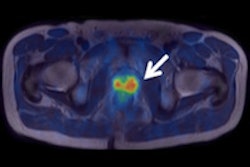

A team from the University of Nottingham in the U.K. has paired a gamma camera with an optical imaging system to create a portable hybrid molecular imaging device. In a clinical pilot study, the handheld hybrid system effectively imaged lymphatic and thyroid tissue as well as drainage from the lacrimal glands, according to the group led by Alan Perkins, PhD.

The device includes a 1.5-mm-thick scintillator and a 1-mm pinhole collimator, which allowed the investigators to optimize image resolution and keep acquisition time under five minutes, according to the society. In their pilot study, the investigators imaged subjects who were undergoing routine molecular imaging procedures such as bone scans or imaging of the thyroid, eye, or lymphatic system.